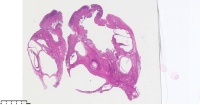

炎性息肉?潴留囊肿?腺体是否有问题?

性别

女

年龄

51岁

临床诊断

一般病史

宫颈赘生物

标本名称

大体所见

息肉。

稳妥起见最好做一做免疫组化。